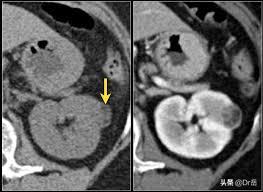

左肾肾癌CT

CT:右肾癌